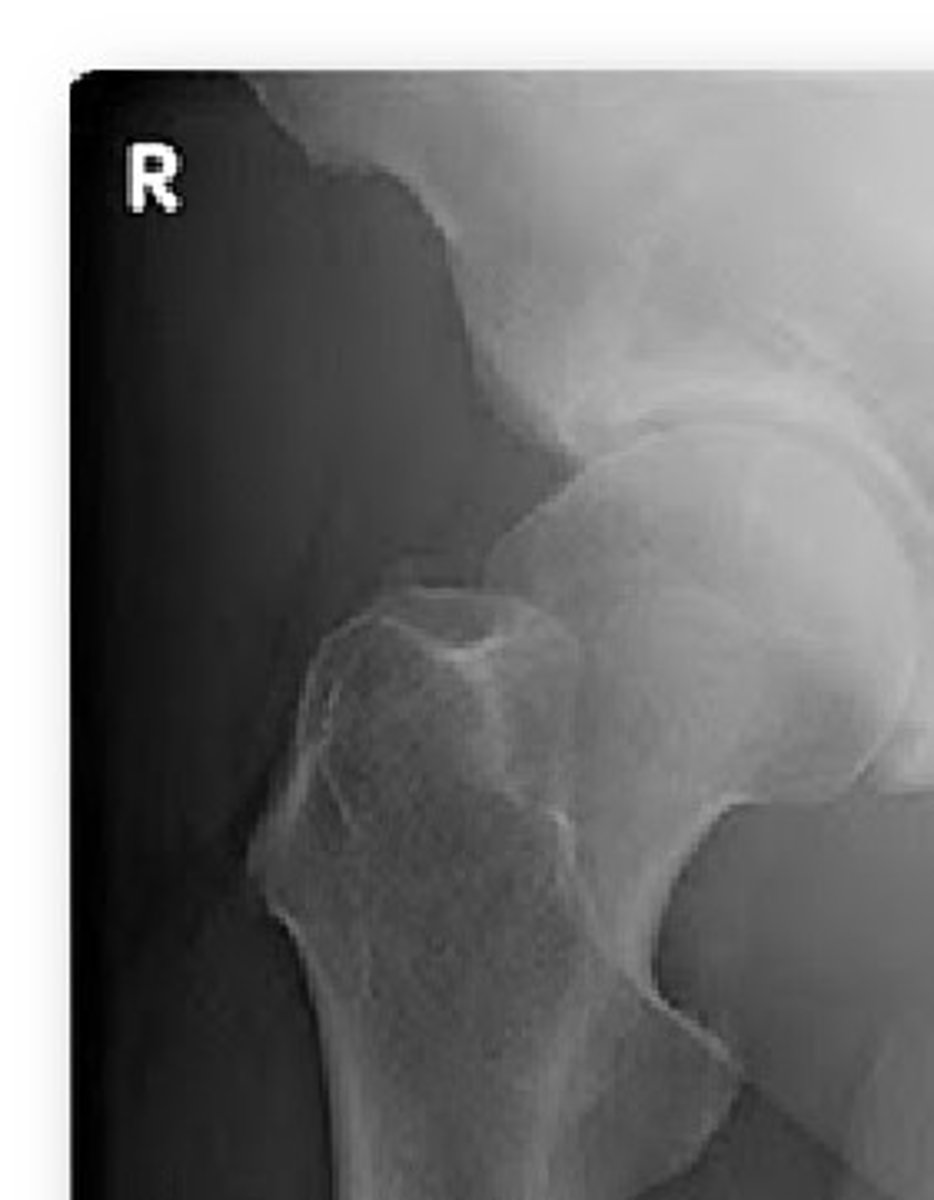

Cam type FAI

overgrowth of the femoral head/neck

Pincer type FAI

overgrowth of the acetabular rim

femoral acetabular impingement (FAI)

impingement between the femoral head/neck and acetabular rim

*occurs secondary to previous hip trauma/pathology with boney overgrowth (osteophytes)

TYPES:

1. cam

2. pincer

*most individuals have a combo of both